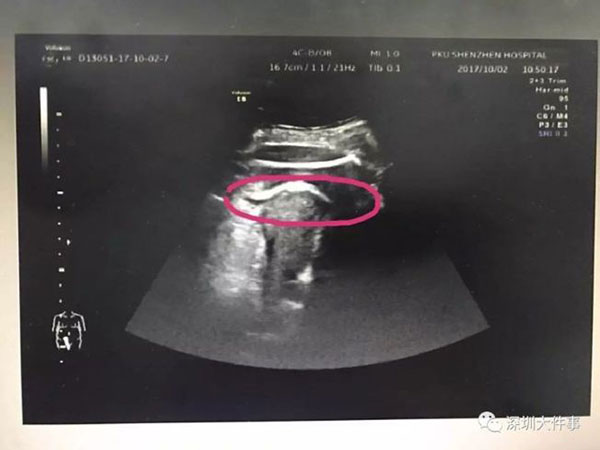

ในเวลาต่อมา แพทย์ได้พบว่า ผนังมดลูกของหญิงรายดังกล่าวฉีกขาด แต่สิ่งที่ทำให้แพทย์ต้องประหลาดใจเป็นอย่างมากนั่นก็คือ ต้นตอที่เป็นสาเหตุคือทารกตัวน้อยในครรภ์ โดยการเตะทะลุผ่านผนังมดลูก ทะลุออกมายังช่องท้อง และขาก็ติดอยู่ตรงบริเวณนั้น

โดยแพทย์เผยว่า ผนังมดลูกของหญิงรายดังกล่าวมีร่องรอยความเสียหายจากการผ่าตัดรักษาเนื้องอกมดลูก เมื่อปี 2559 ส่งผลให้เนื้อเยื่อบริเวณผนังมดลูกบาง และเสี่ยงที่จะฉีกขาดได้ง่าย ซึ่งนับว่าเป็นอันตรายมาก อาจทำให้เธอเกิดภาวะช็อกจากการเสียเลือดมาก หรืออาจติดเชื้อจนถึงแก่ชีวิตได้